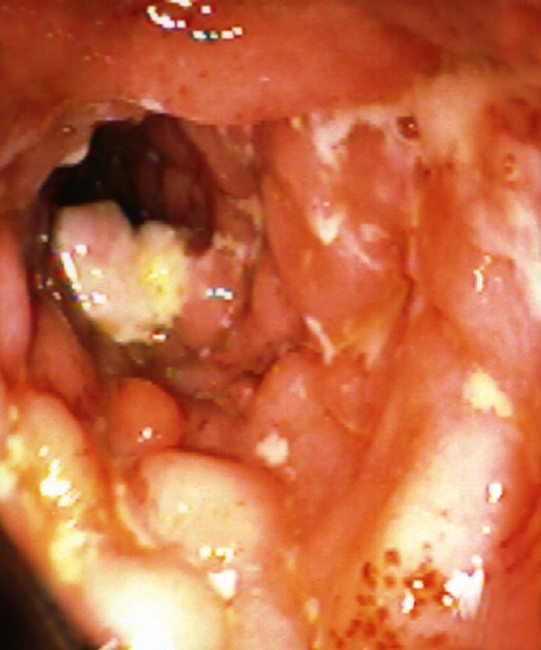

UC - distribution of disease

sx of UC